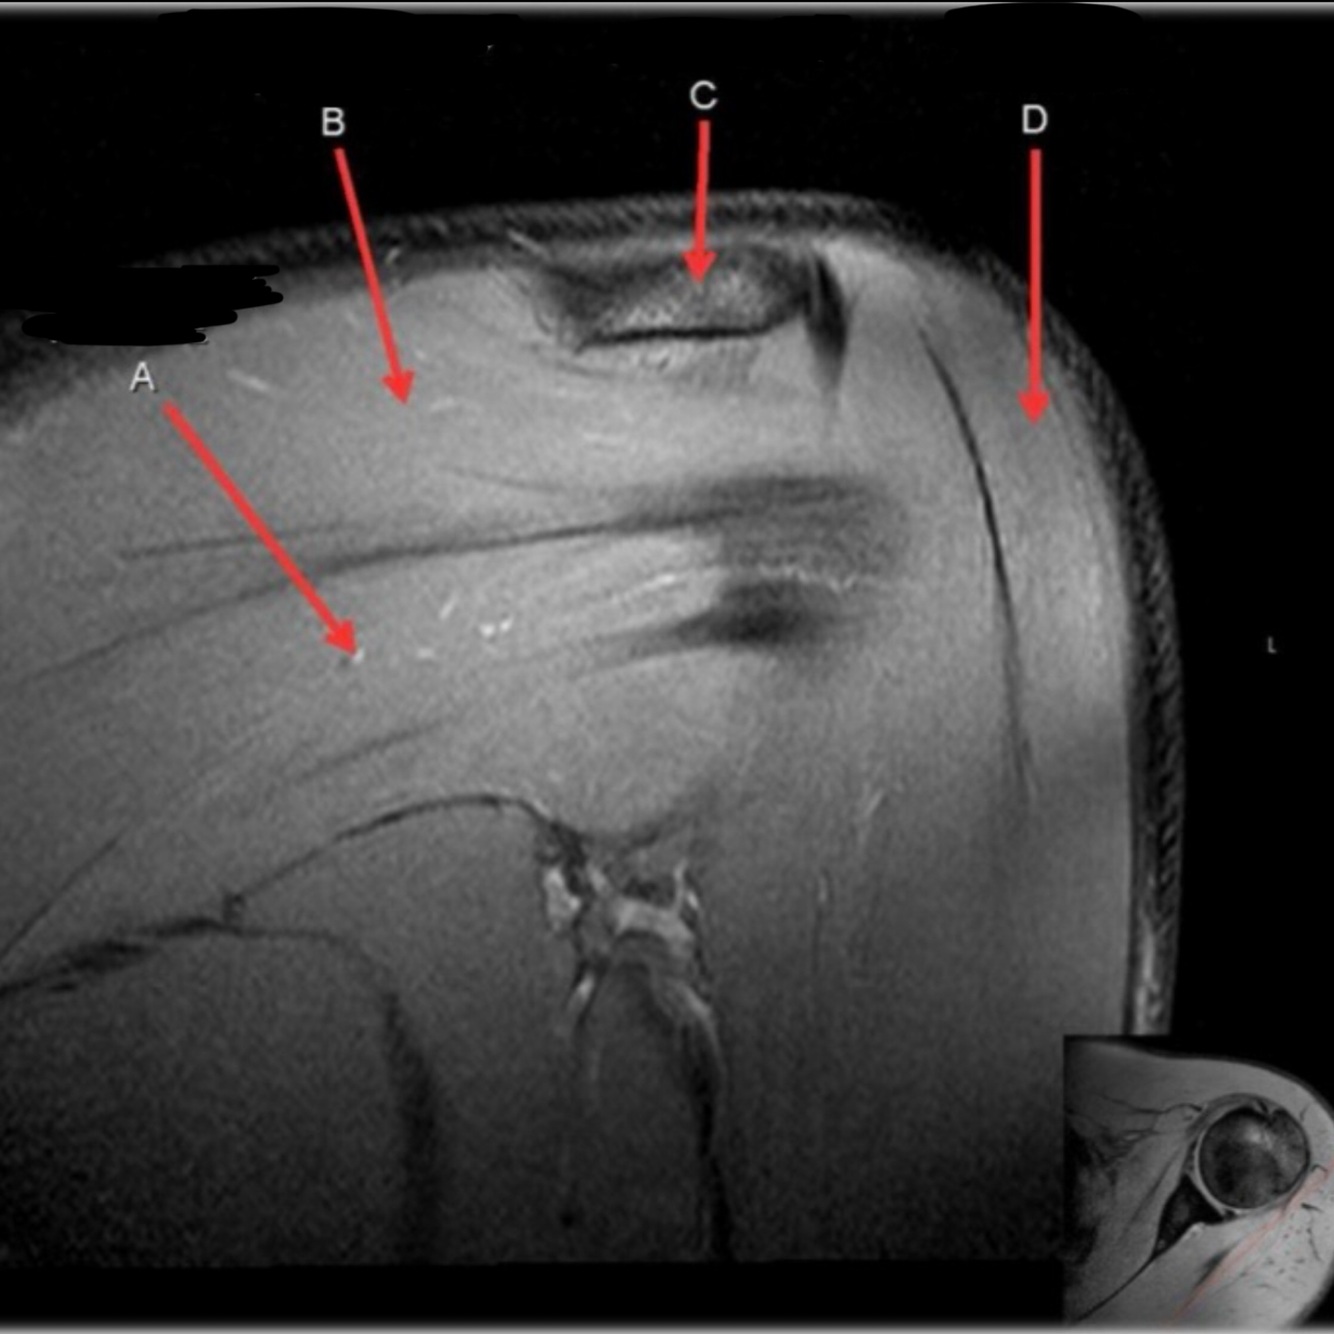

Q

What is letter A?

SUPRASPINATUS TENDON

What is letter B?

ACROMION

What is letter D?

A

SUPRASPINATUS MUSCLE

How well did you know this?

17

What is letter C?

18

DELTOID MUSCLE

19

SPINE OF SCAPULA

20

21

INFRASPINATUS TENDON

22